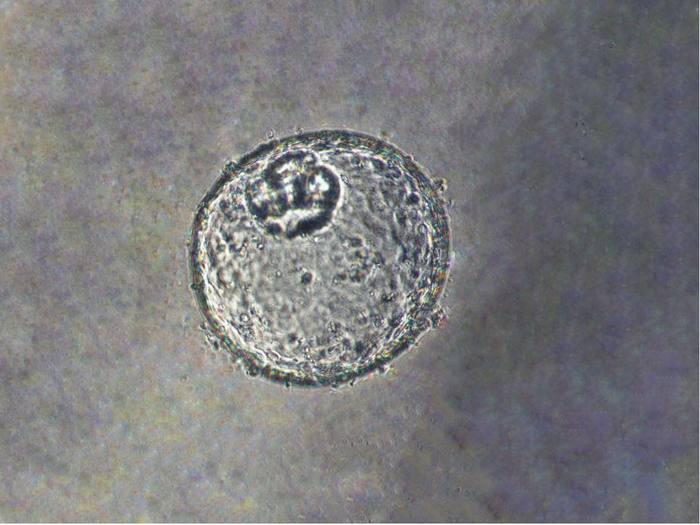

Meltzer and a team of experts in cell biology, epigenomics, lipid profiling and big data analysis created the GEJ disease model by taking normal human biopsy tissue from patients receiving upper endoscopies. Organoids comprise three-dimensional collections of cells derived from stem cells that can replicate characteristics of an organ or what an organ does, such as making specific kinds of cells.

Using clustered regularly interspaced palindromic repeats (CRISPR/Cas9), a gene editing technology, the researchers then knocked out two key tumor suppressor genes (TP53 and CDKN2A) in the organoids. Dual knockout of these genes caused cells to become more cancerous, with more rapid growth and microscopic features closer to malignancy. These altered organoids also formed tumors in immunodeficient mice.